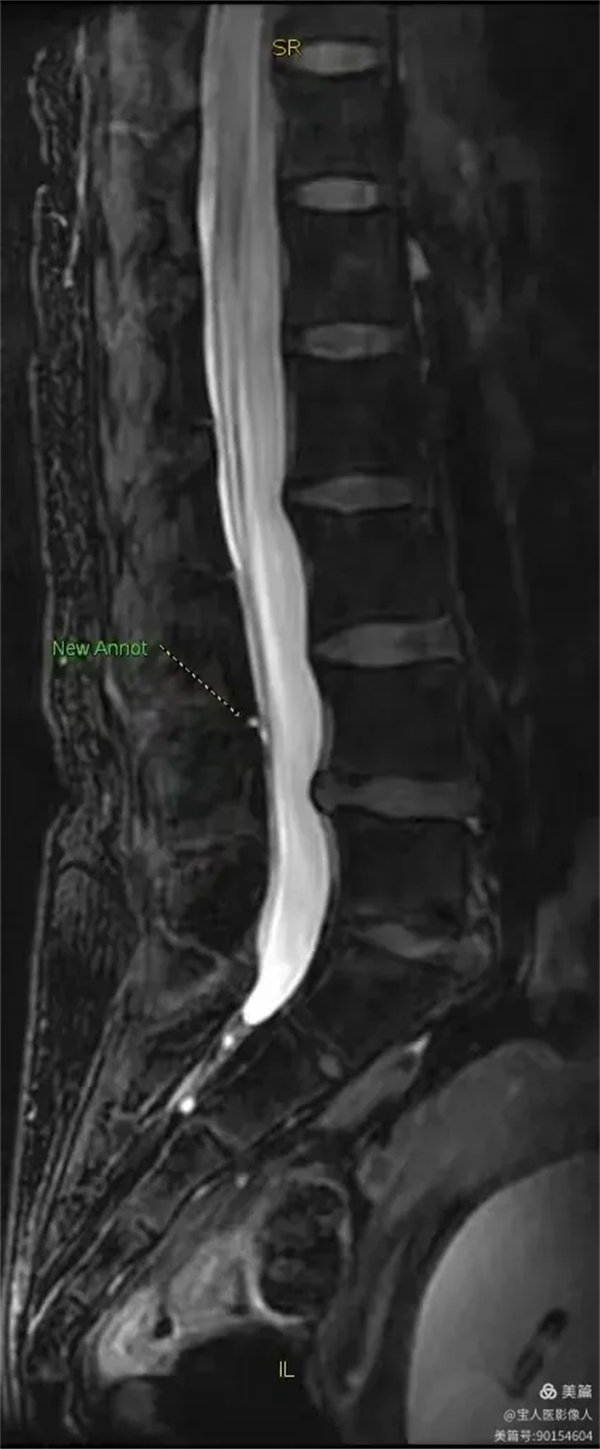

最大密度側面圖,顯示腰段硬膜囊內腦脊液(高信號)。